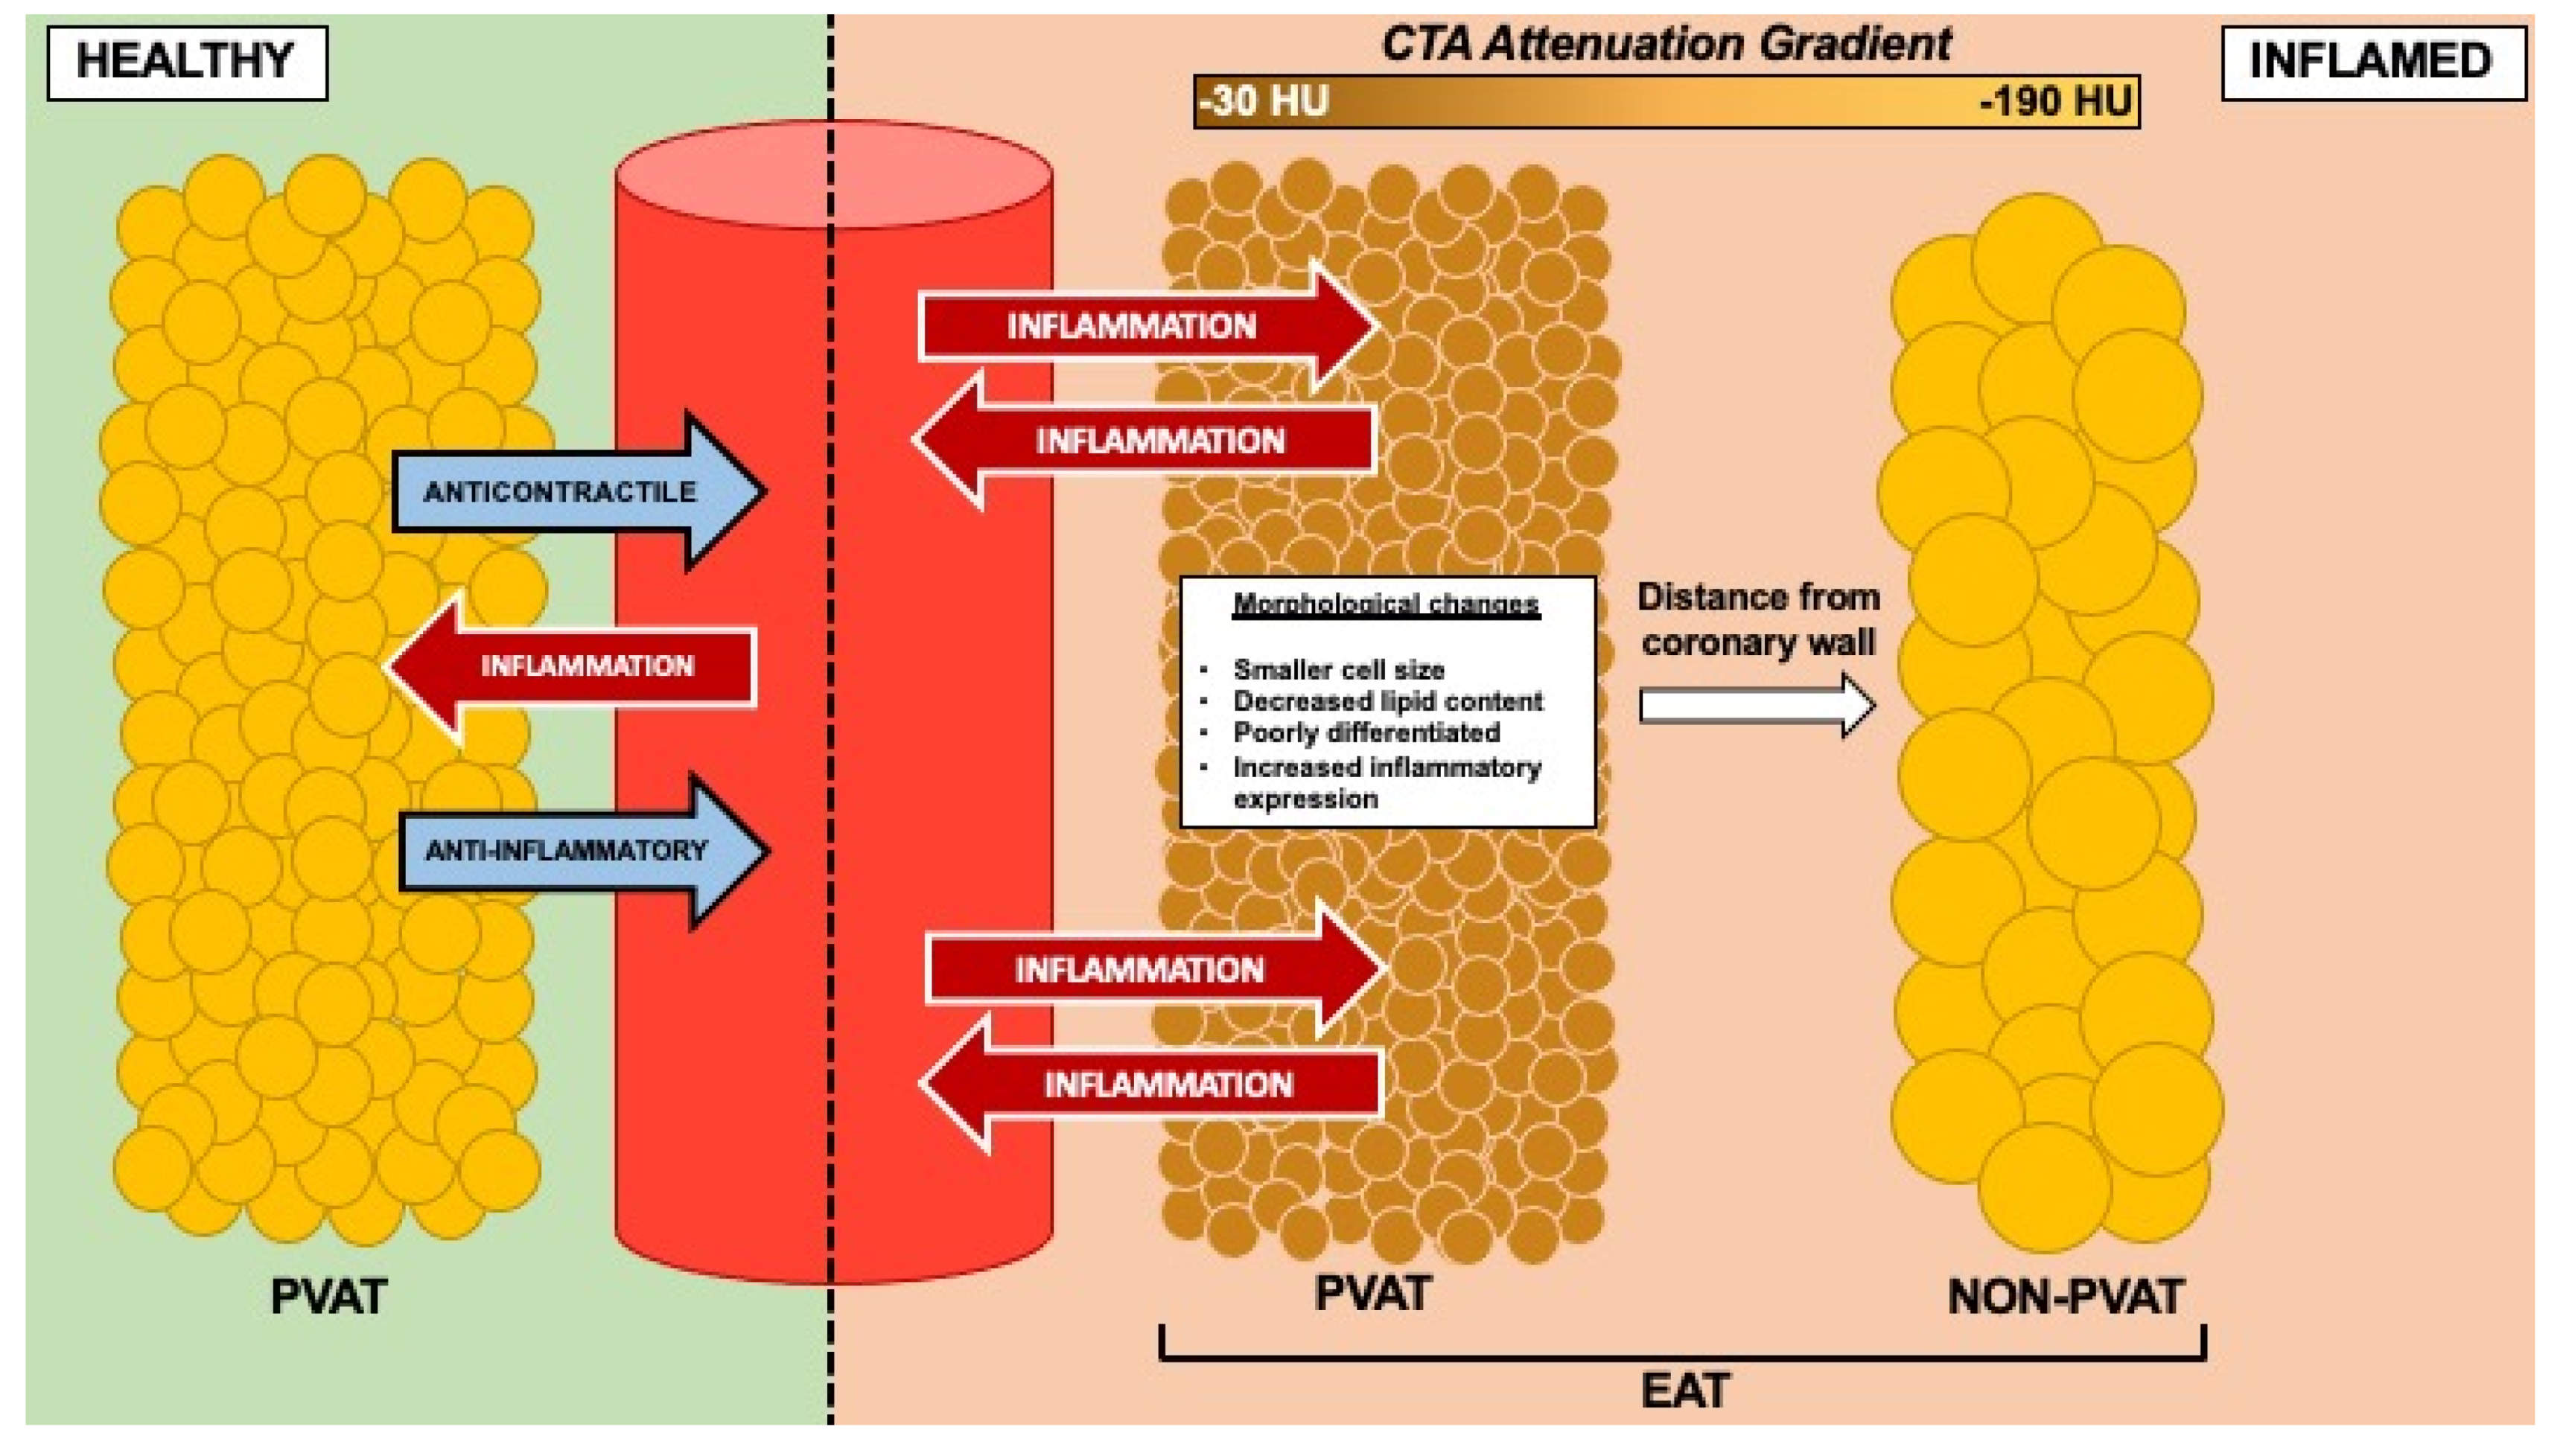

4. Association of Inflammation and Cardiac Adipose Tissue

4.1. Local Epicardial Adipose Tissue (EAT) Inflammation in Coronary Artery Disease (CAD)

5.2. Pericoronary Fat Attenuation Index